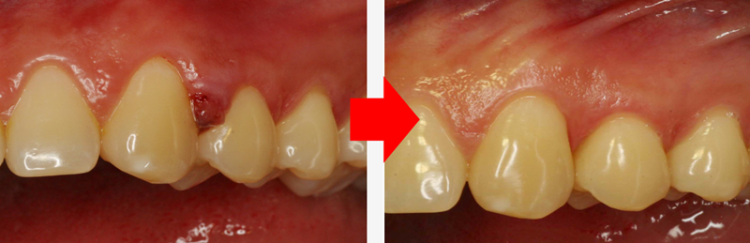

더 위험한 것은 잇몸뼈가 공기 중에 노출되면 뼈가 녹는 속도가 훨씬 빠르고 잇몸이 약해지기 때문에 좋은 결과를 기대하기는 어렵습니다. 3232235521_UMJFRCEv_1ae2fad53fafee3cb764ae2ee81e54d4db3ad922.png 그렇다면 잇몸 속 치석을 방치하고 잇몸 내려앉음이 발생하는데도 손 놓고 기다려야 하는지 마음이 안 좋으실 텐데요. 3232235521_IaTqZzGP_4055b8d6ace5f5edbe40d099fe24107132a7aa88.png

물방울레이저로 치아와 잇몸 사이의 틈에 에너지를 주사해 그 어떤 절개나 봉합 없이 제거를 도와드립니다.